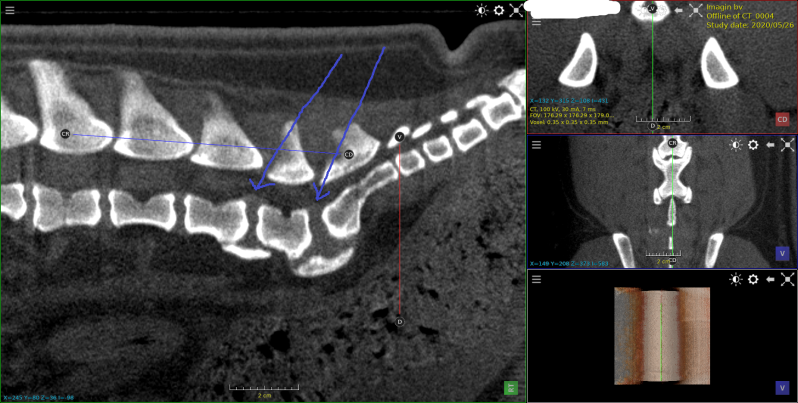

cocker met hernia  c2-c3

Twee gevallen van een ernstige cervicale discus hernia.